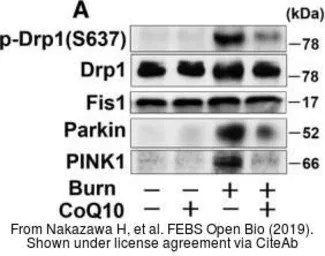

The data was published in the journal FEBS Open Bio in 2019.PMID: 30761259